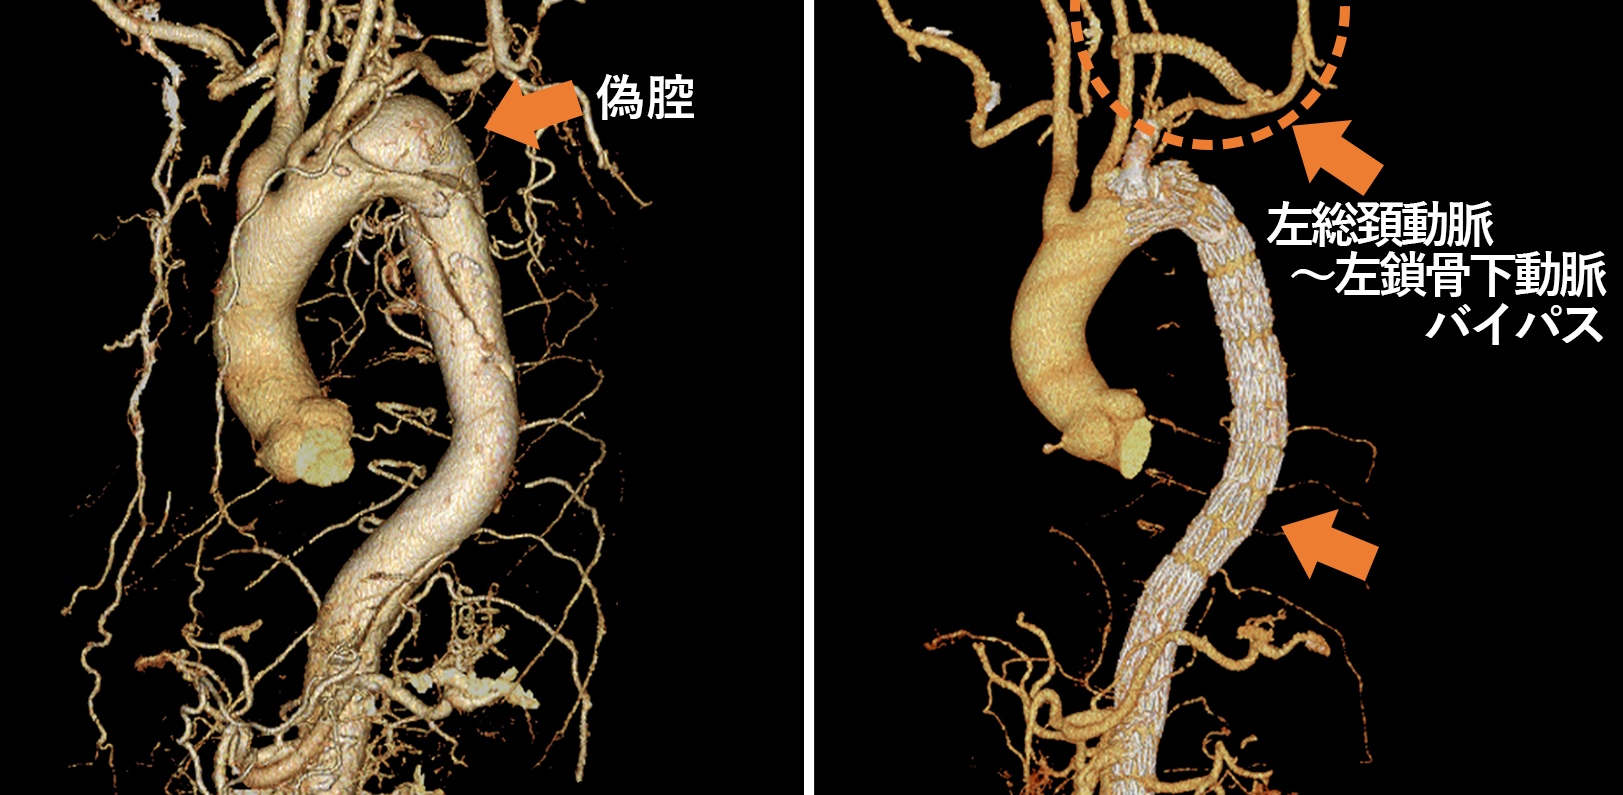

大動脈瘤

大動脈疾患は、特に突然死の原因として心筋梗塞の次に多い疾患とも言われており、その予防と、救急対応が地域にとって重要な問題です。埼玉県東部地域における緊急手術対応可能な医療機関として、一人でも多くの人命を救助できるように、緊急手術にも積極的に対応しております。近隣の地域のみならず、緊急症例においては埼玉県全域および近隣の都道府県からのご依頼にも対応します。

胸部大動脈瘤や腹部大動脈瘤に対する治療としては、人工血管と置換する手術が基本的な根治的治療ですが、形態的な適応と年齢や手術侵襲による影響を考慮して、ステントグラフト挿入術も行っております。 他の心臓血管疾患と同様に大動脈疾患も早期発見と予防が重要です。特に大動脈疾患は、リスクファクターをお持ちの方や、ご家族に大動脈疾患を患ったことのある方には一度検査を受けることをお勧めしています。当科では、動脈硬化の評価とともに、大動脈瘤のスクリーニング検査や、動脈硬化の判定なども外来で行っております。スクリーニング検査は主にCTの大動脈の評価を行っております。